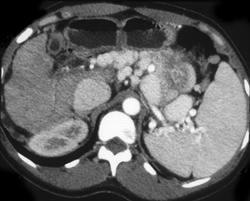

Renal Cell Carcinoma in Dialysis Patient